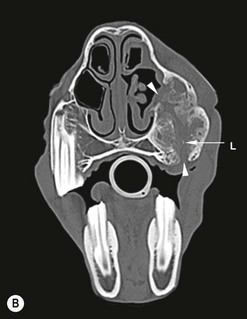

image image image

Fig. 13.43 Radiograph (A) and CT images (B and C) of a compound odontoma in a 2-year-old TB colt.

(Images courtesy of J. Easley.)